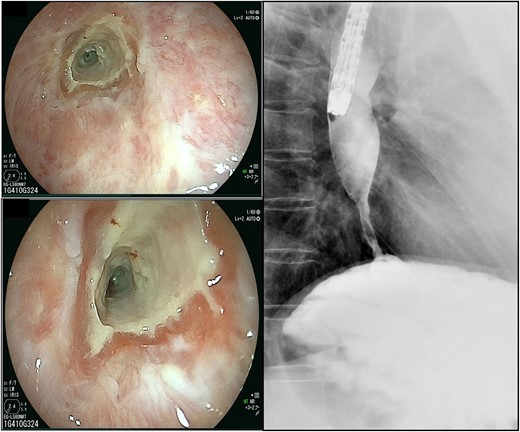

A 58-year-old woman with severe stricture of the lower esophagus was referred to our institution. She had been receiving medication to treat GERD at multiple facilities for the past 5 years. Six months prior to the referral, she underwent laparoscopic esophageal repair for esophageal rupture (Fig. 1a). After the rupture, she eventually presented with NE (Fig. 1b), a condition that consequently led to severe stenosis of the lower esophagus (Fig. 2). Multiple biopsies did not confirm any malignancy in the esophagus, and endoscopic balloon dilatation temporarily enabled endoscopic observation of the gastro-duodenum, which had no significant abnormal findings, but failed to relieve the constriction. Computed tomography revealed a 10-mm hypervascular mass on the anterior wall of the duodenum, suggestive of a gastrointestinal stromal tumor (Fig. 3); there were no findings suggestive of esophageal malignancy. Pathological diagnosis of the duodenal mass could not be determined because the endoscope used for endoscopic ultrasound-fine needle aspiration could not pass through the esophageal stricture.

Previous conditions of the esophagus. Esophageal rupture accompanied by a massive mediastinal abscess (arrowheads). Necrotizing esophagitis of the lower esophagus.

The scars continued down the esophagus, extending beyond 23 cm from the incisors, while the lower esophagus to the gastroesophageal junction was severely constricted.